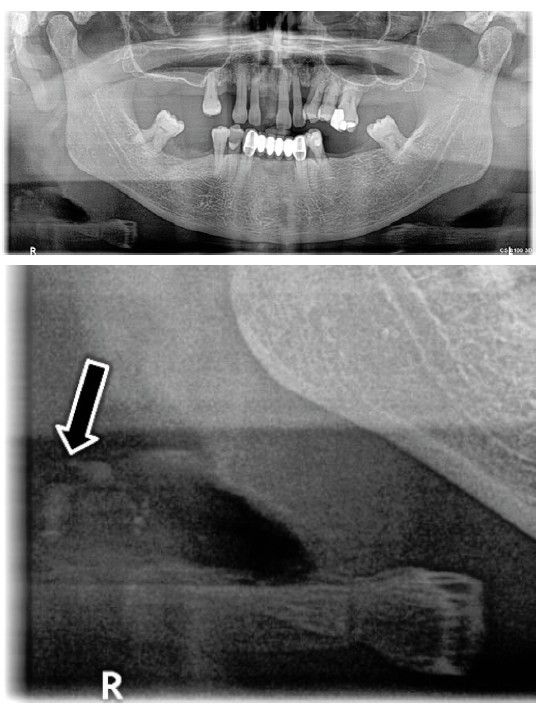

Paciente 2

Se presenta una paciente de 77 años, fumadora de 10 cigarrillos al día, con periodontitis estadio IV generalizado grado C. Ha sido tratada periodontalmente en nuestra consulta donde continúa realizando sus revisiones periódicas. En su última cita de mantenimiento en 2024, al preguntarle si se había producido alguna modificación en su historia médica, nos comunicó que acababa de ser diagnosticada de calcificaciones en la carótida izquierda a raíz de observar hipotensión arterial en el brazo izquierdo frente al derecho. Con esta sintomatología, su médico de familia decidió solicitarle un eco-Doppler, en el que encontraron dichas placas de ateroma calcificadas.

Ante las explicaciones de la paciente, se revisó su última radiografía panorámica, de 2016 y se pudo observar que en ese momento ya presentaba varias calcificaciones entre la 2ª, 3ª y 4ª vértebras cervicales, pequeñas, circulares, de tipo nodular, que, sin embargo, en ese momento, pasaron desapercibidas (Figuras 4 y 5).

En esta paciente, el diagnóstico de ateromas en la carótida se realizó después de la aparición de algunos síntomas, aunque afortunadamente antes de que ocurrieran episodios cardiovasculares o cerebrovasculares oclusivos. Este caso denota la importancia de identificar la presencia de este tipo de imágenes en las radiografías panorámicas, lo que permitiría un diagnóstico precoz y, en consecuencia, la prevención de complicaciones derivadas.

Cuando son pequeñas tienen una apariencia radiográfica circular. Sin embargo, los grandes ateromas tienen forma lineal o rectangular delgada. En el paciente 1, las calcificaciones eran bilaterales, grandes, rectangulares, irregulares, situadas entre 1-2 cm posteroinferiores al ángulo mandibular, suprayacentes a los tejidos blandos prevertebrales. En el paciente 2, sin embargo, las calcificaciones aparecían unilateralmente, más pequeñas, circulares y múltiples, suprayacentes a los tejidos blandos prevertebrales y adyacentes al hioides.

En el paciente 1 y 3 las calcificaciones aparecían en la bifurcación carotídea, el lugar más frecuente de aparición, según Friedlander y Friedlander8. En los pacientes 2 y 3 los ateromas carotídeos eran unilaterales, izquierdo en el paciente 2 y derecho en el paciente 3, coincidentes con las imágenes calcificadas de manera unilateral que se habían observado en la radiografía panorámica solicitada únicamente por motivos de control periodontal.